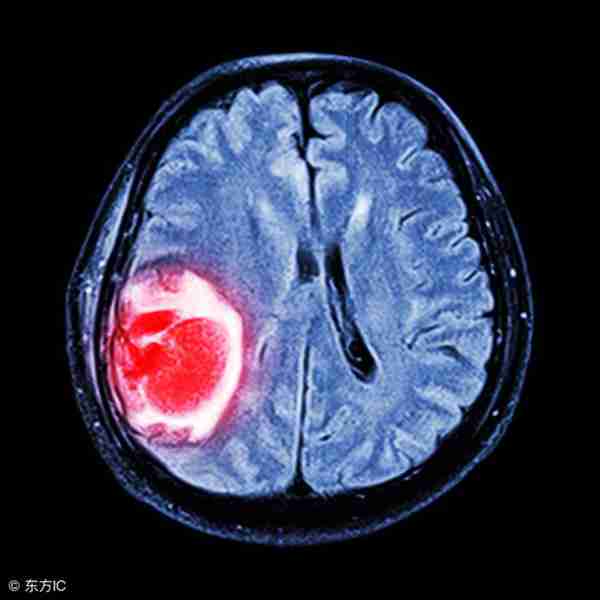

做一个MRI检查是比较费时的,可能需要半个小时,甚至是一个小时,导致MRI预约时间长,限制了MRI的应用。对于急诊的患者,也不适合做MRI检查,例如怀疑急性脑出血的患者,首选做CT检查,CT只需要几十秒钟就搞定了,核磁检查时间太长,有可能会延误治疗时间,导致严重的后果。